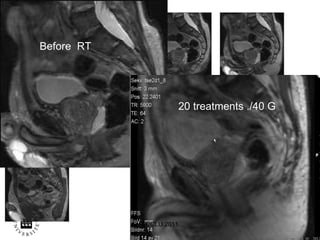

ECCLU 2011 Before  RT 20 treatments ./40 G